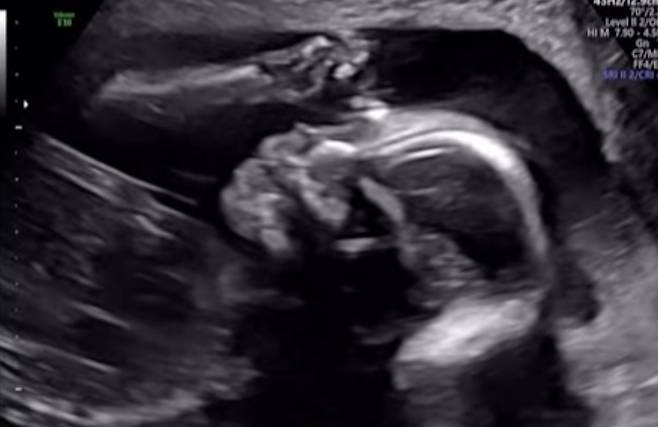

임정희가 이와 함께 공개한 초음파 영상에는 23주차 태아의 모습이 담겼다.

임정희의 설명대로 입을 오물거리는 모습이 시선을 모았다.

그러면서 "아기의 태명은 봉봉이다. 엄마 뱃속에서 입을 오물거리는 귀여운 봉봉이 모습 살짝 보여드리겠다"고 덧붙였다.

임정희가 이와 함께 공개한 초음파 영상에는 23주차 태아의 모습이 담겼다. 임정희의 설명대로 입을 오물거리는 모습이 시선을 모았다.